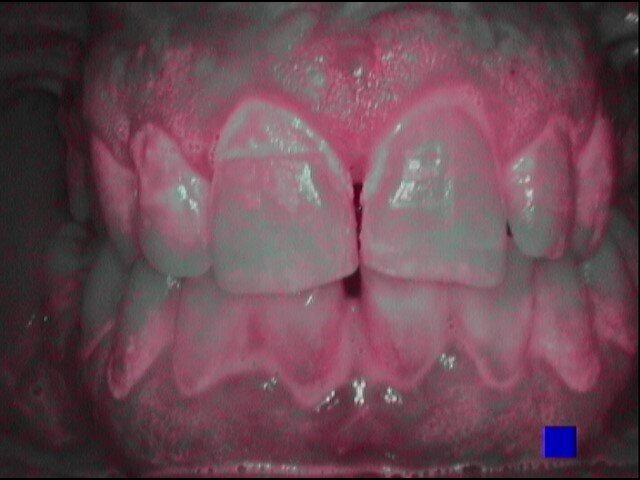

Vengono rilevati gli indici clinici e vengono condivise con il paziente le immagini raccolte con la videocamera intraorale, così da motivarlo di fronte alla presenza di tartaro e infiammazione gengivale e mostrargli le aree critiche. Viene apposto il rilevatore di placca alla fluorescina ed illuminato da una lampada fotopolimeralizzante, che permette di visualizzare la topografia del biofilm batterico (D-BIOTEK-TECNICHE)2, in modo da condividere con il paziente i siti più a rischio del cavo orale (Figg. 1a-2f).